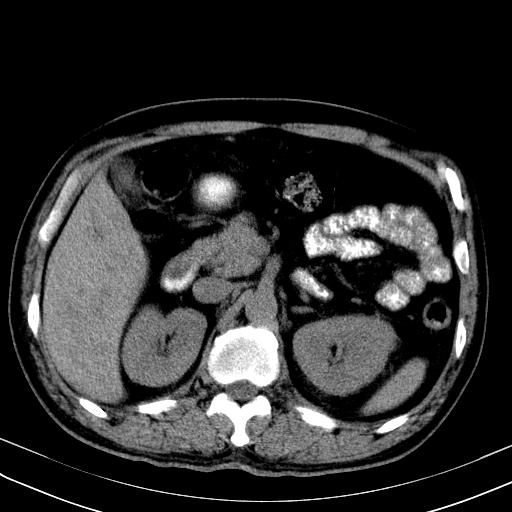

先行ct平扫,纵膈内多发软组织影,ct值约为36hu,以下为增强扫描和腹部平扫。

经典?纵膈多发肿大淋巴结。腹膜后未见异常。

还见胃窦壁增厚!转移亦有可能!

1)考虑淋巴瘤。2)双侧少量胸腔积液。

大家看看肝脏右叶片状低密度影是什么改变啊?